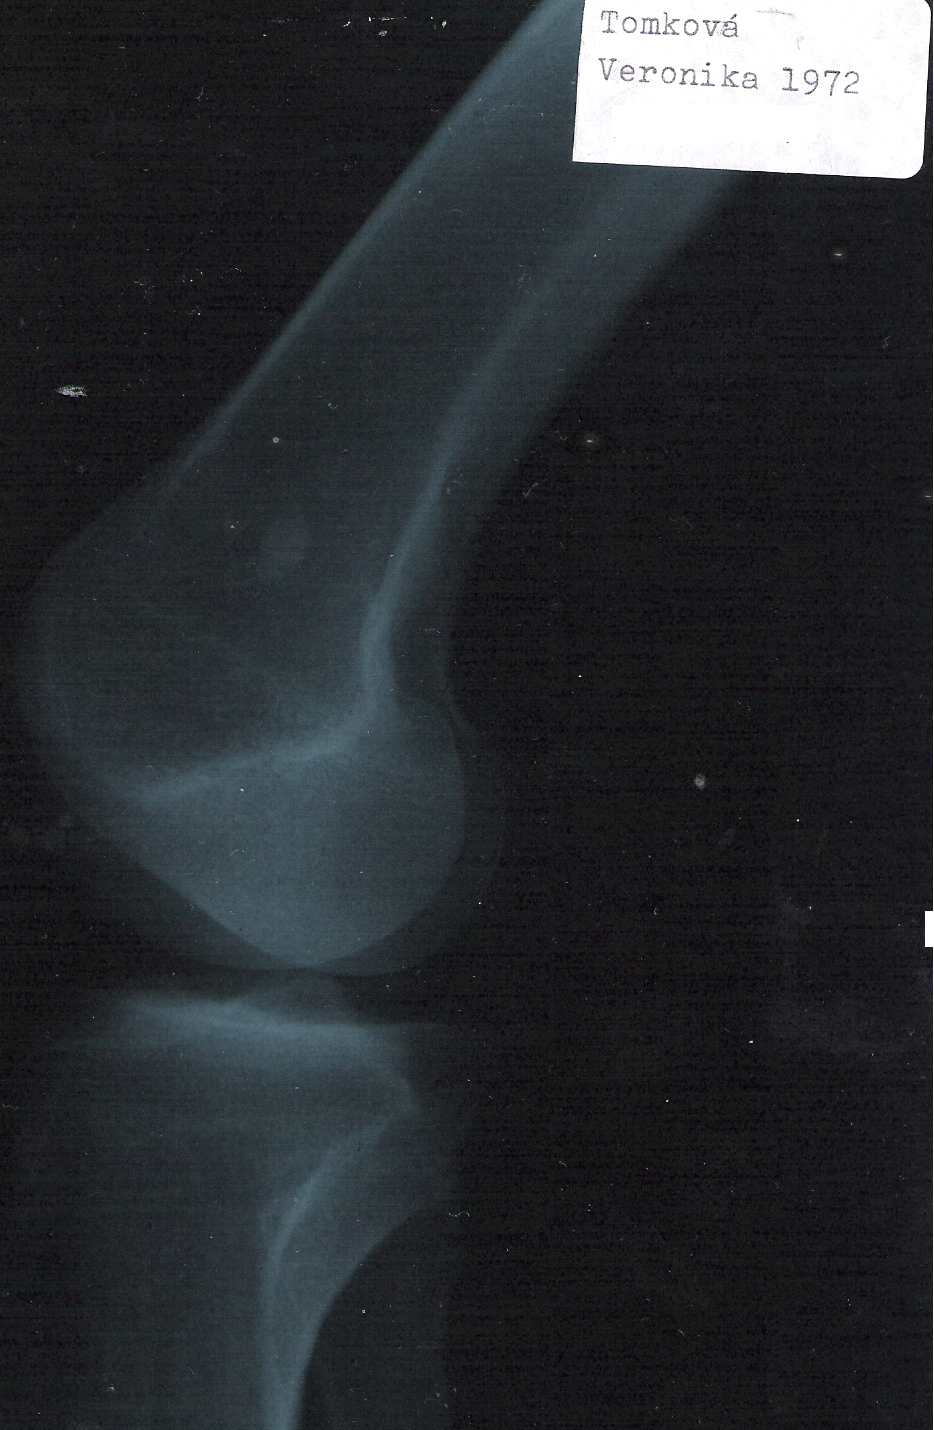

Je mi velmi tazke pisat o sebe a prosit o pomoc. Nakolko uz niekolko rokou mam problemi s kolenami ako som uz mala prosbu aj v minulych vyzvach. Bolesti sa stupnuju viav a viac. Ked som chodila po lekaroch bolo mi vysvetlene, ze operacia nieje mozna nakolko nemaju ako prichitit nahradne kosti alebo ako sa to povie pretoze moje kosti prachniveju. Tym ze sa to neda operovat casto mi vyskajuju kolena a dostane sa tam voda ktora sa zapali a velmi to bol. lekar povedal cim viac sa bude voda tahat tzm viac sa bude hromadit a zapalovat. Je to obrovsak bolest. Bolo mi navrnute jedno riesenie a to liecenie kmenovymi bunkami. No zial som to doteraz neriesila az teraz nakolko musim sa starat o mamku a kolena ukrutne bolia a tvori sa zapalova voda. Tato lecba vraj velmi zlepsuje chrupavky klbovych - artozy. najcastejsie sa ponuka tao liecba ak je 1 az 2 stupen poskodenia. Tieto liecebne metody podctupuju najme sportovci co maju po tejto metode velmi dobre vysledky. Mozem aj poukazat nato, ze pred par rok.odvisielala TV Markiza o mojich problemoch s kolenami v Reflexe.

Dobrý deň. Strašný smútok mam. Veľmi chcem sa postarať o svoju mamku nakoľko je už na vozíčku už 28r. Som sama na mamku a tak sa to podpísalo na mojom zdraví. Moje kolená sú veľmi opotrebované až tak že vyskakuju a až 2 stupeň rozpadá ia kolenych kosti s tým že operovať sa to nedá nakoľko kosti prachniveju. Jediná možnosť je liečba kmeňovými bunkami. Prosím pekné pomôžte nám. Veľmi chcem sa postarať o mamku a bez Vás to nedáme. ANJELI